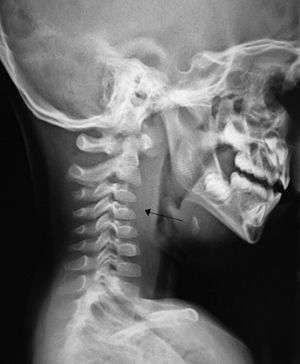

If more than half of the size of the C2 vertebra, it may indicate retropharyngeal abscess.[3]